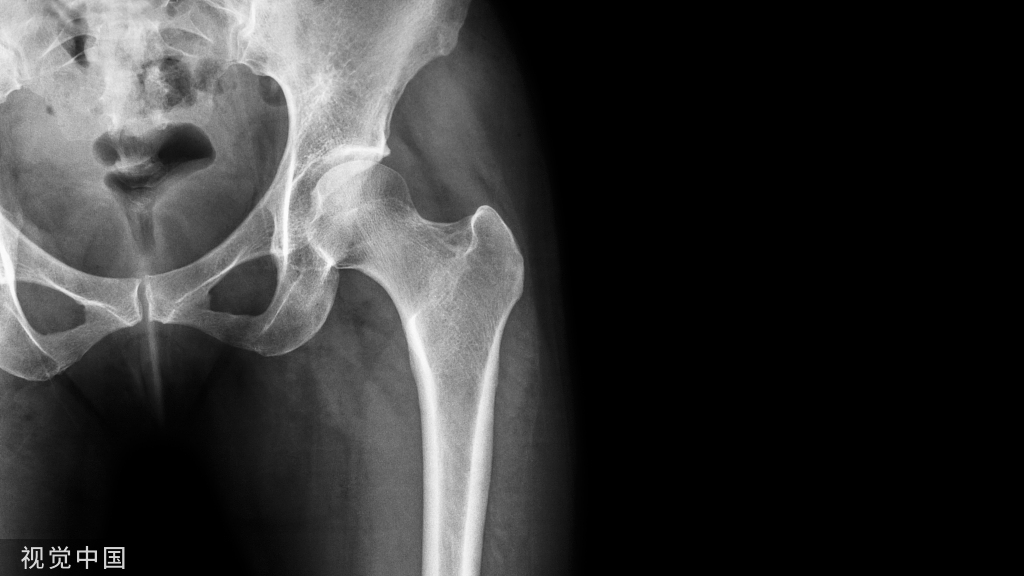

X线平片是检出脆性骨折,特别是胸、腰椎压缩性骨折的首选方法。常规胸、腰椎X线侧位摄片的范围应分别包括胸4至腰1和胸12至腰5椎体,基于胸、腰椎侧位X线影像并采用Genant目视半定量判定方法,椎体压缩性骨折的程度分类如下: